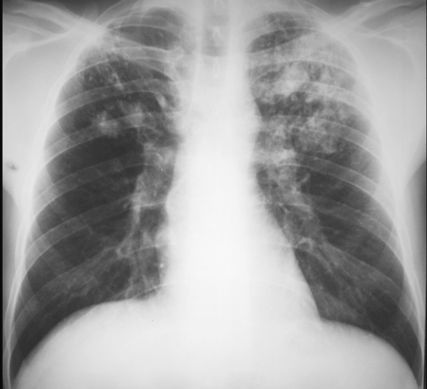

GRUŹLICA

RTG